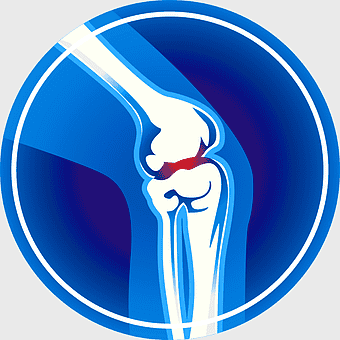

512x512px

knee pain symptoms, joint pain illustration, arthritis blue icon, osteoarthritis medical diagram, human body joint health, bone condition visual, joint discomfort -